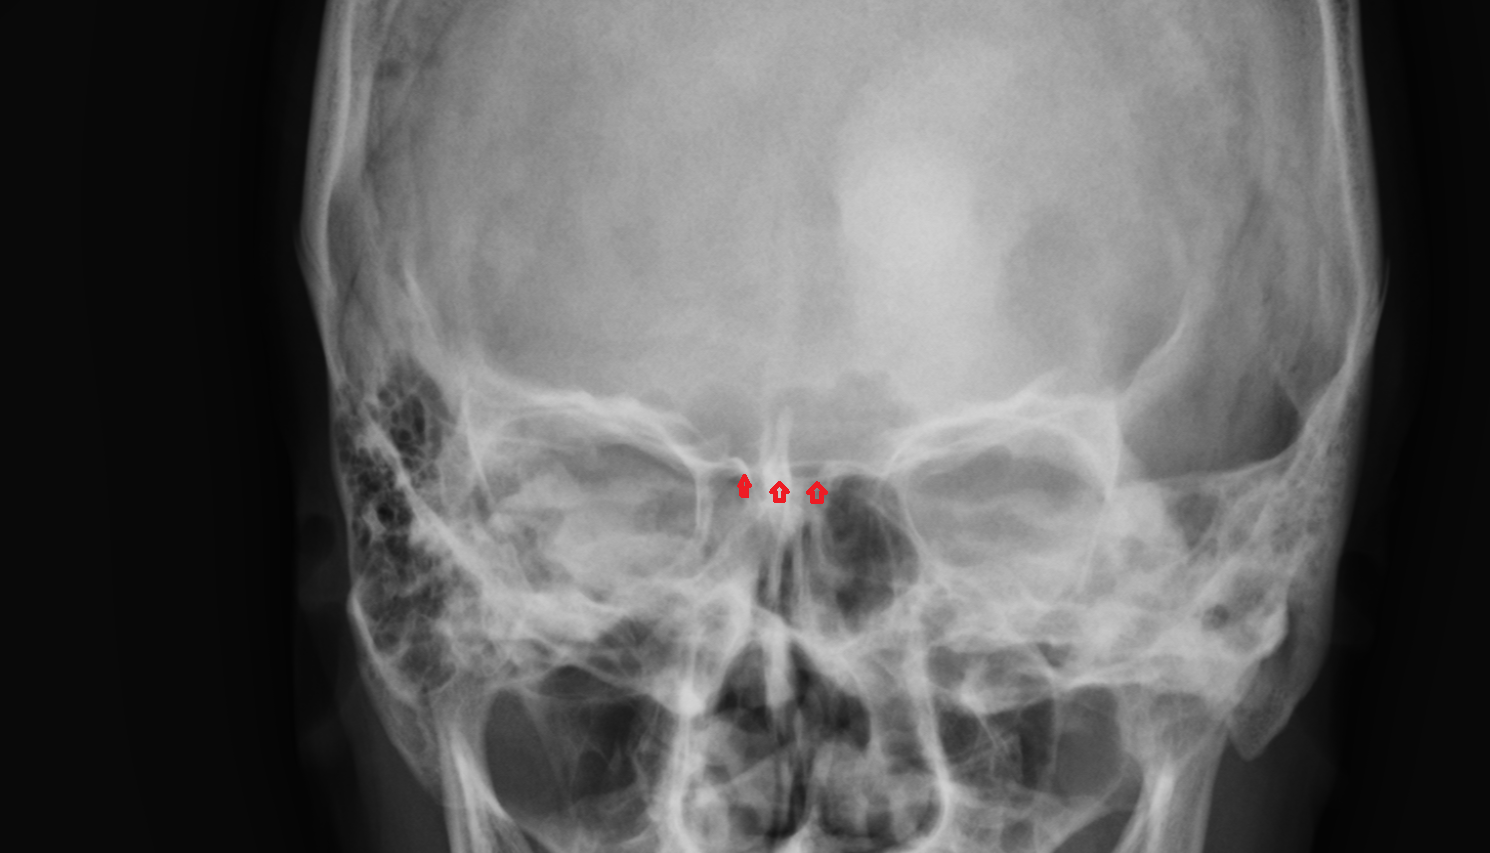

- Choana